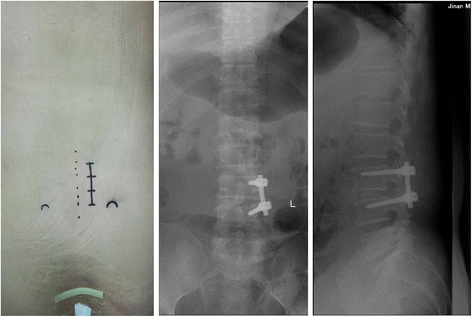

This project was approved by the Institutional Review Board of the General Hospital of Jinan Military. The present retrospective study recruited 78 patients with the treatment of single-level pedicle screw fixation and lumbar interbody fusion at L4–L5 or L5–S1 from January 2010 to January 2013. All patients had suffered from low back pain, severe unilateral radicular pain, or neurological symptoms. All patients underwent at least 6 months of conservative management before surgery, with no response or an inadequate response. All patients were diagnosed with plain radiographs, CT scans, and MRI. Patients were included if they were aged between 40–70 years and without spondylolisthesis. Patients who were significantly obese (body mass index ≥35 kg/m2), had previous lumbar fusion or discectomy, lumbar tumors, severe osteoporosis, active inflection, RA, or other underlying conditions were excluded from the study. From January 2010 to May 2012, the patients were treated with MIS TLIF with BPS fixation (group A, Fig. 1), and since May 2012, all patients were treated with UPS fixation (group B, Fig. 2). Demographics and procedure data for the two groups are listed in Table 1.